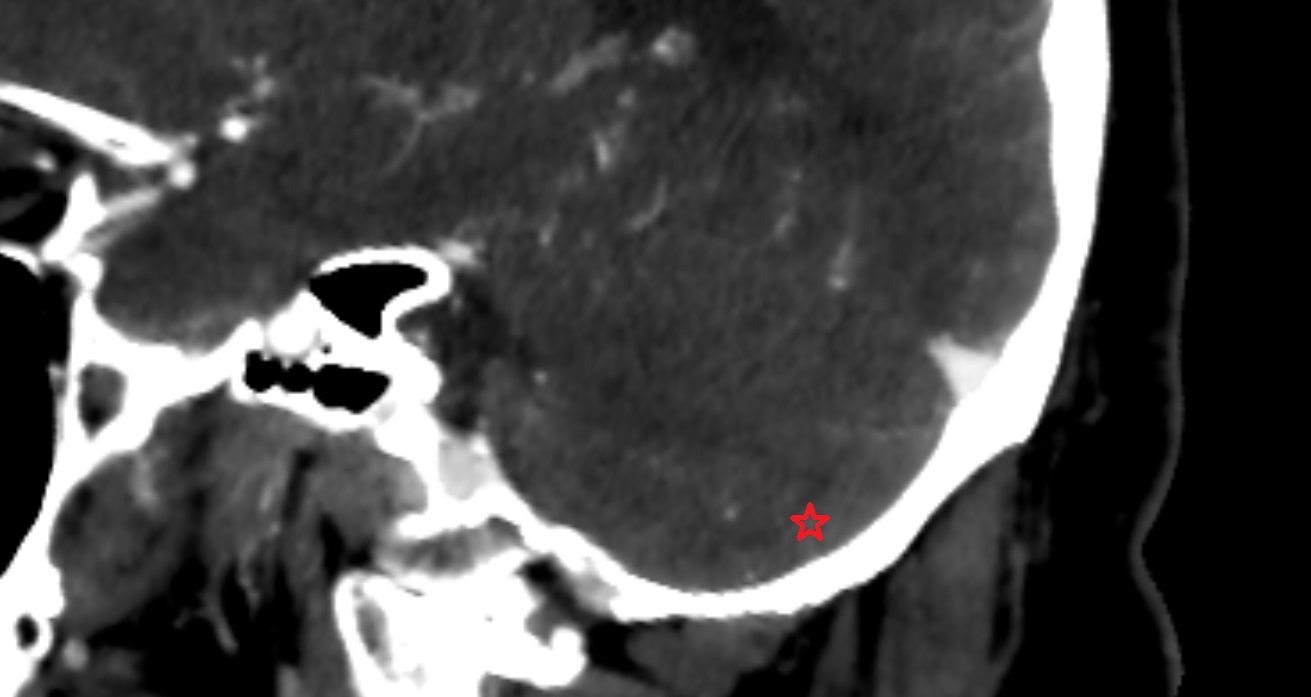

- Cerebellum